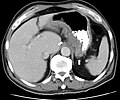

Kompjuterizirana tomografija (CT) i magnetska rezonancija (MR) su slikovne pretrage korisne za otkrivanje promjena tankog crijeva pomoću enteroklize (metoda kojom se kroz jednjak, želudac, duodenum i jejunum barijeva kaša ubrizgava sve do ileuma).[94] Ovim pretragama se također mogu otkriti intraabdominalne komplikacije Crohnove bolesti, poput apscesa, opstrukcija i fistula u tankom crijevu.[95] Magnetska rezonancija (MR) je metoda slikovnog prikaza tankog crijeva i komplikacija, no ona je skuplja i manje dostupna.[96]